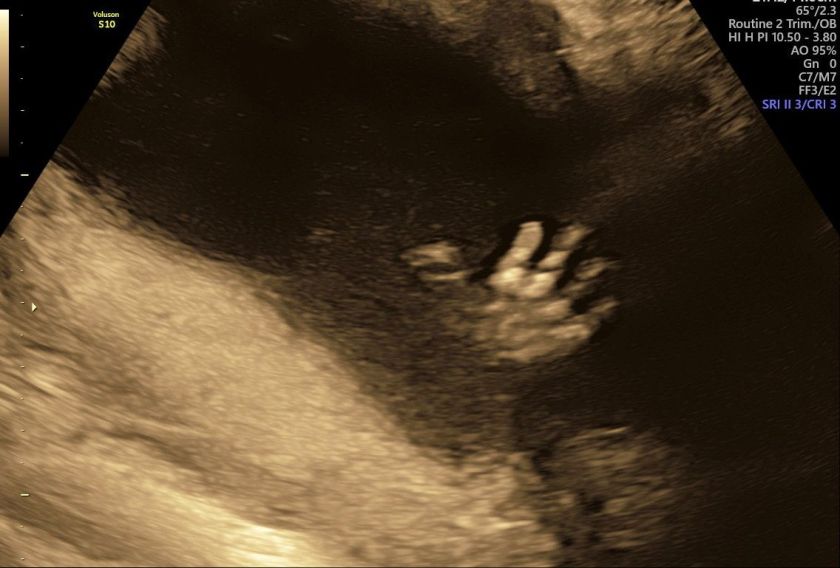

After this the countdown to the first echo started – since it the Netherlands they only do the first one at 10 weeks. So on 14 July, we got to see our little shrimp for the first time:

At this point, the baby is about 4 cm big and the size of a date – isn’t that crazy?